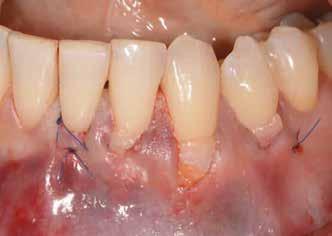

teljes mértékben megtartott, a vertikális augmentáció a tervezettnek megfelelő eredményű volt (13–15. ábra), a klinikai kép is ennek megfelelően alakult, optimális menynyiségű keratinizált ínnyel és azt adekvát sebészi technika eredményeképpen megtartott vesztibulummal (16–17. ábra). Az alsó és felső állcsontba 4-4 darab Bredent COPA Sky implantátumot ültettük, D1-D2 csontminőség mellett,

35 Ncm primer stabilitást mértünk. Nyílt gyógyulási protokollt alkalmazva az ínyformázókat is behelyeztük, amelyek körül az ínyt csomós öltésekkel zártuk (18–20. ábra) Amennyiben lehetséges, mindig nyílt gyógyulási protokollt választunk, így biztosítva elegendő időt a lágyrészek maturációjához (29). Kiemelendő, hogy az irodalmi adatoknak (30, 31, 32) és saját tapasztalatunknak megfelelően az íny biotípusának jelentős, pozitív irányú változását észleltük. Az implantátumokra 180 nap gyógyulási időszakot követően (minden implantátum stabilitása Periotesttel –8-as értékű volt) hagyományos lenyomatvételi módszer és egyéni értékű artikulátor használatával a fogtechnikus (D1 Dental Kft., Garamvári Csaba) overdenture típusú fogpótlást készített (21. ábra)

A protetikai rehabilitációt követően 9 hónappal az alveoláris struktúrák stabilak, a röntgenfelvételen a csontállomány megtartott, a beteg panaszmentes, rágó funkciója kifogástalan, az esztétikai eredménnyel teljes mértékben elégedett (22–23. ábra)